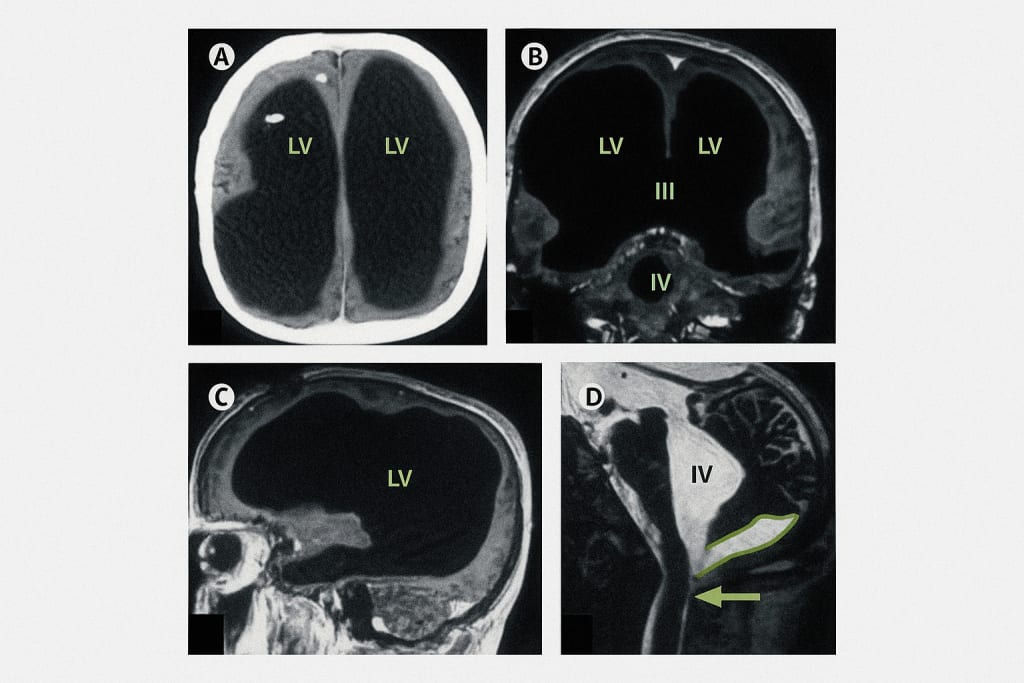

His skull was filled with fluid — so much so that his brain had been compressed into a sliver of tissue, only a few millimeters thick. That’s right: nearly all of his brain was gone. And yet, this man lived what appeared to be a completely normal life. He had a job in public service. He was married. He had two children. He functioned like any ordinary adult. There were no signs of severe cognitive delay or disability. In fact, his IQ was slightly below average — but nothing that raised red flags.

This bizarre and shocking case made headlines across the globe, leaving scientists puzzled and fascinated. It turns out, the man had lived with chronic hydrocephalus — a condition where fluid builds up in the brain — since birth. Most people with severe cases don’t survive infancy. But somehow, his brain adapted over decades, reshaping itself in ways we never imagined possible.